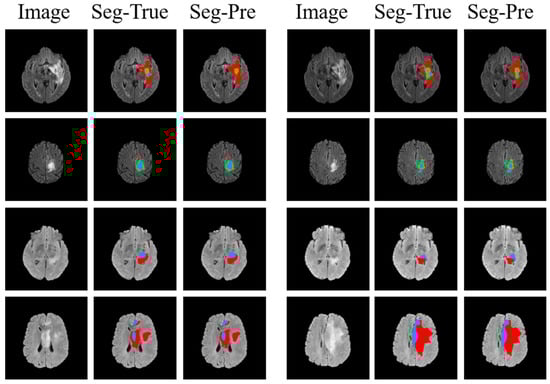

4.3.1. Segmentation Results

4.3.3. Comparison of Segmentation and Explainability